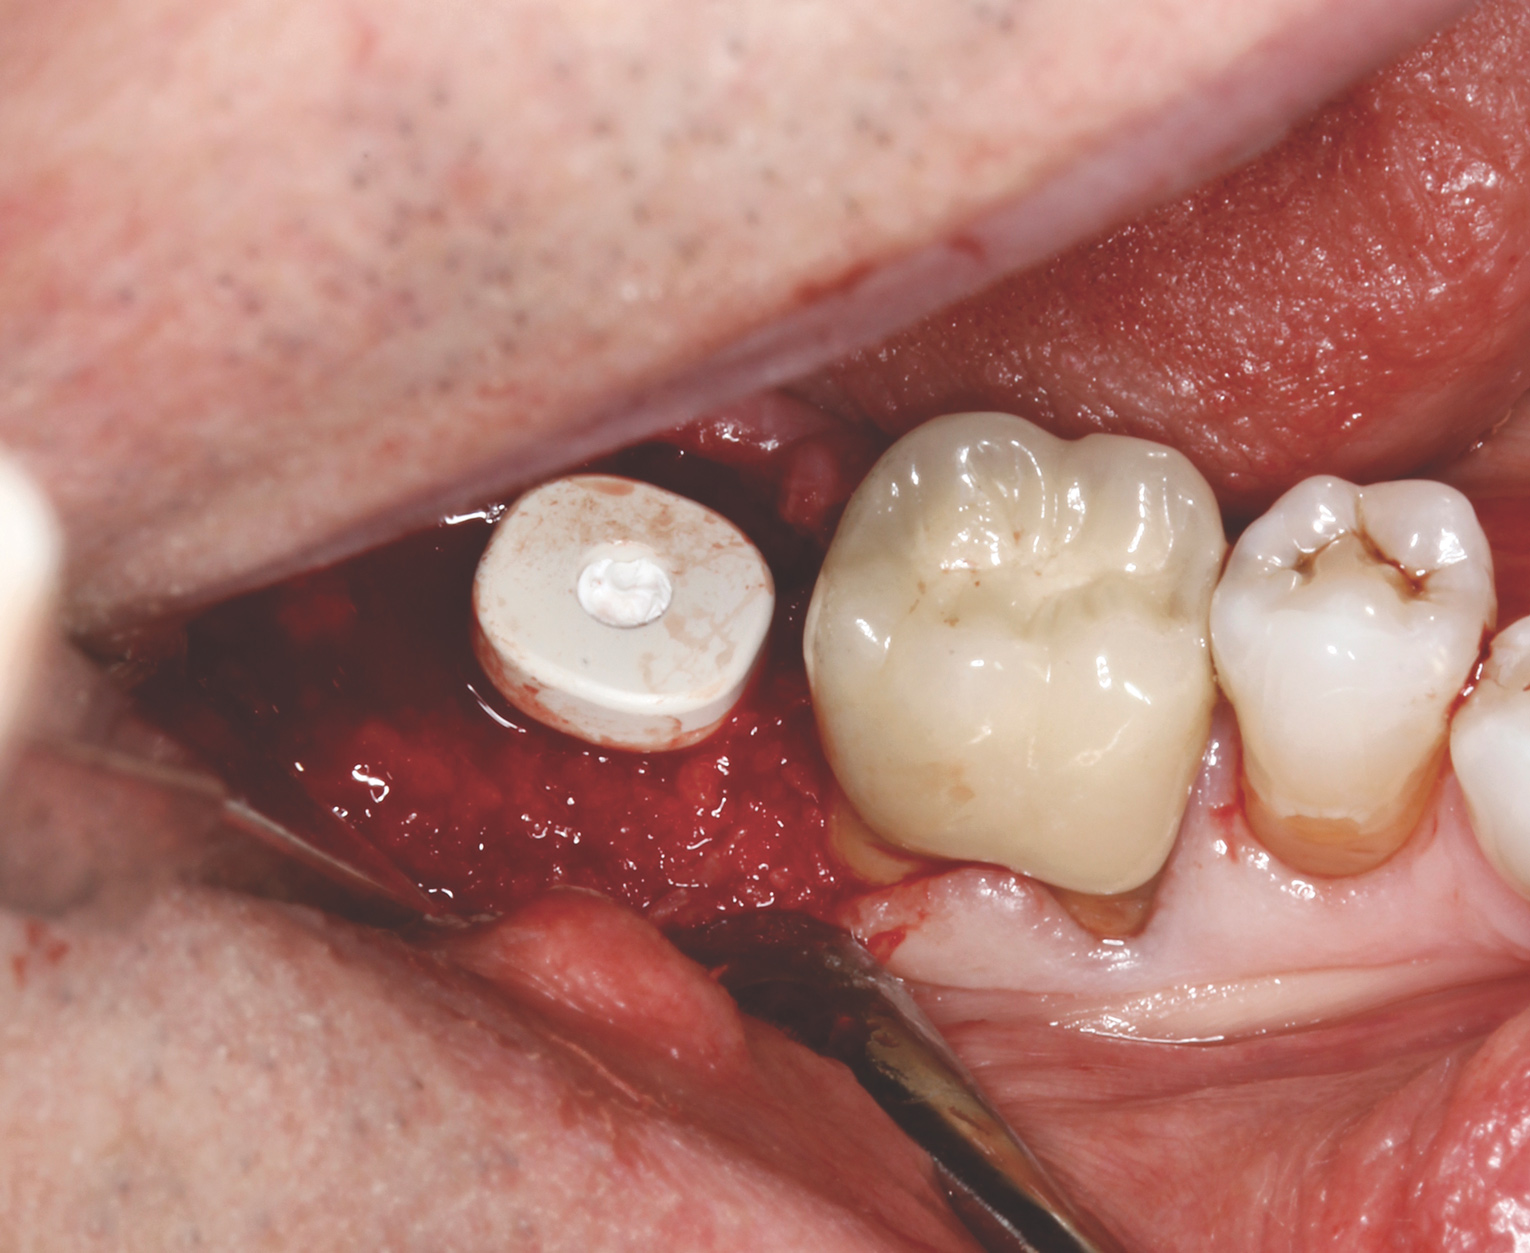

After clinical evaluation, CBCT assessment with a dynamic navigation fiducial was followed by planning for immediate implant placement. This included evaluation of inferior alveolar nerve position, undercut, buccal plate dehiscence, implant positioning in the defect, and retention screw path. The patient was taken to surgery under intravenous and local anesthesia with removal of the mandibular right second and third molar teeth. The sites were aggressively debrided with a mesiobuccal root dehiscence noted, and site development followed with the use of dynamic navigation (Figure 13).

Implant insertion (5.5 mm x 13 mm NobelActive®, Nobel Biocare, nobelbiocare.com) gave excellent primary stability, was level with the residual buccal bone, and achieved an ISQ reading of 74 (Figure 14). Lingual bone contouring (to avoid abutment impingement) was followed with implant gap grafting, which included the mesiobuccal root defect and adjacent extraction site, using mineralized particulate cortico-cancellous allograft (enCore®, Osteogenics Biomedical). A 7 mm x 8 mm poly-ether-ether-ketone (PEEK) healing abutment was inserted and the access opening filled with PTFE tape (Figure 15). A single layer of dHACM (Figure 16) was inserted on the bone graft with tissue forceps and saturated with saline to seal the implant-soft-tissue interface. Suturing with 4-0 chromic gut secured the site, using inverse "figure 8" at the anterior and interrupted sutures at the posterior margin (Figure 17).

Fig 14. Extraction site, with mesiobuccal bone dehiscence concealed under soft tissue, and immediate implant placement with ISQ post in position.

Figure 14